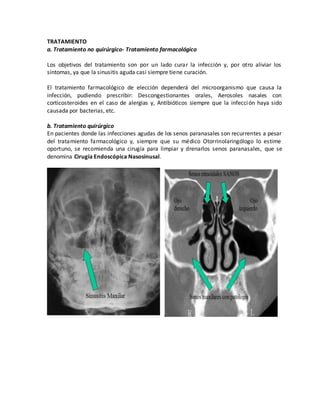

TRATAMIENTO

a. Tratamiento no quirúrgico- Tratamiento farmacológico

Los objetivos del tratamiento son por un lado curar la infección y, por otro aliviar los

síntomas, ya que la sinusitis aguda casi siempre tiene curación.

El tratamiento farmacológico de elección dependerá del microorganismo que causa la

infección, pudiendo prescribir: Descongestionantes orales, Aerosoles nasales con

corticosteroides en el caso de alergias y, Antibióticos siempre que la infección haya sido

causada por bacterias, etc.

b. Tratamiento quirúrgico

En pacientes donde las infecciones agudas de los senos paranasales son recurrentes a pesar

del tratamiento farmacológico y, siempre que su médico Otorrinolaringólogo lo estime

oportuno, se recomienda una cirugía para limpiar y drenarlos senos paranasales, que se

denomina Cirugía Endoscópica Nasosinusal.